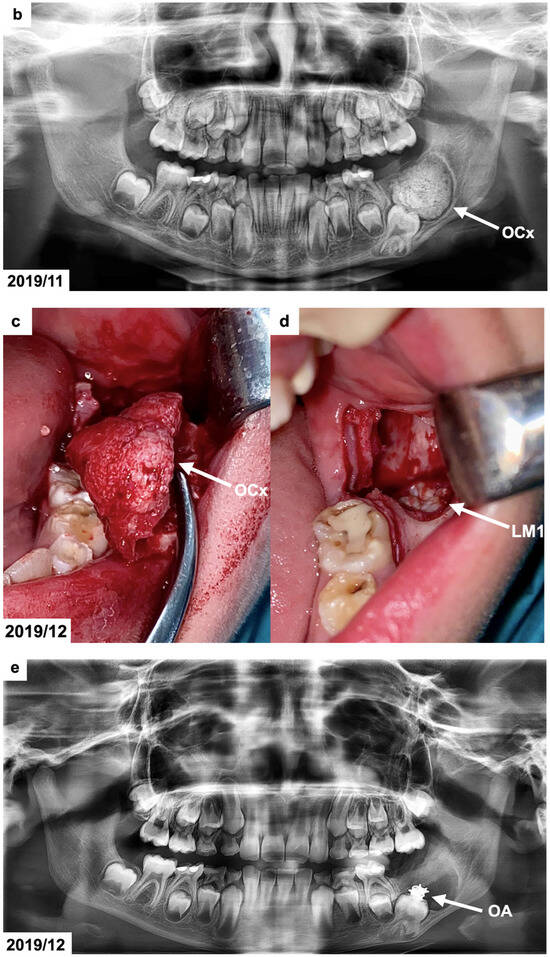

Figure 1.

(a) Intraoral photographs before surgical and orthodontic treatment. The patient was 8 years and 10 months old. (b) Panoramic radiograph before the treatment, presenting the odontogenic tumor in the left mandible molar region (OCx = complex odontoma). The patient was 8 years and 10 months old. (c,d) Intraoral photographs taken during the surgical removal of the tumor exposing the occlusal surface of the permanent lower left first molar (OCx = complex odontoma, LM1 = lower left first permanent molar). The patient was 8 years and 11 months old. (e) Panoramic radiograph after the surgical treatment and bonding of the orthodontic attachment (OA = orthodontic attachment). The patient was 8 years and 11 months old. (f) Panoramic radiograph 1 year after the removal of the tumor showing the orthodontic attachment bonded to the occlusal surface of the permanent lower left first molar (OA = orthodontic attachment). The patient was 10 years and 1 month old. (g) Intraoral photographs of spontaneously erupted permanent lower left first molar after removal of the orthodontic attachment. The patient was 10 years and 11 months old. (h) Panoramic radiograph 4 years after the surgical and orthodontic treatment (LM1 = lower left first permanent molar). The patient was 12 years and 7 months old. (i) Intraoral photographs 4 years after the surgical and orthodontic treatment showing the erupted permanent lower left first molar and its position in the dental arch. The patient was 12 years and 7 months old.

The panoramic radiograph (Figure 1b), which was provided by the patient, indicated the presence of a calcified lesion with a radiolucent rim and an adjacent cortical bone layer with a diameter of approx. 3 cm at the distal area of the mandibular first permanent molar. To precisely define the size and position of the tumor, the patient was referred for cone-beam computed tomography (CBCT). The CBCT examination showed a focal area with a calcified mass with the radiodensity of hard dental tissues surrounded by a narrow radiolucent zone on the left side in the molar region of the mandible. The dimensions of the lesion were 25 × 20 × 17 mm. The radiological picture indicated the presence of a complex odontoma. This lesion extended to the lower border of the mandible. The position of the neighboring first permanent molar was altered by the tumor as the tooth was moved downward and mesially. The roots of the affected molar were still developing (app. 2/3 of the final root length). The upper part of the tumor was not covered by the alveolar bone by 20 × 6 mm.

The surgery was performed under local anesthesia using lignocaine 2% with noradrenaline. In the retromolar area of the mandible, a triangular incision and a mucoperiosteal flap retraction were performed, exposing the rough surface of the tumor and the adjacent bone. A bony layer covering the lesion topically and buccally was removed using a round surgical bur with constant saline solution irrigation. After the tumor exposure, it was separated and removed entirely without damaging the unerupted first permanent molar (Figure 1c,d). The cavity was rinsed with a Metronidazole solution. The orthodontic attachment was bonded to the occlusal surface of the exposed tooth (Figure 1e). The flap was repositioned, and sutures were placed. The removed tumor was submitted for histopathological examination. Post-operatively, the patient was given an antibiotic (amoxicillin 500 mg/clavulanic acid 125 mg) every 12 h for 7 days. A follow-up visit was scheduled after 7 days of uneventful healing, and the sutures were removed. No post-operative complications were noted.

The H&E staining of decalcified section showed the composition of dentinal tissues arranged in a haphazard manner with irregular borders, confirming the clinical–radiographic diagnosis of complex odontoma.

The lower removable plate with an extension to attach the elastic from the button bonded on the exposed impacted molar was prepared in March 2020. However, due to the eruption of the COVID-19 pandemic, it was not delivered to the patient after surgery. The university clinic was only treating emergencies for the next few months, and the patient came back after 1 year, in February 2021. The patient reported a spontaneous eruption of the impacted maxillary. The occlusal surface of the lower left first permanent molar with a bonded button was visible during the clinical examination. The panoramic radiograph (Figure 1f) revealed a distinct occlusal movement of the impacted tooth and normal healing after the removal of the tumor. In December 2021, the mandibular left first permanent molar erupted in the oral cavity (Figure 1g). No pathologies were present on the panoramic radiograph except for the bending of the distal root of the affected molar. The patient has received an activator with an expansion screw to correct his Class II relations and maxillary crowding. In August 2023, the impacted molar tooth erupted into occlusion, and the root development was finished (Figure 1h,i). A marked dilaceration of its distal root could be noticed, which was caused by the presence of a tumor in proximity to the developing, neighboring first molar. The prognosis of the affected molar was estimated as favorable in the long term if good oral hygiene is maintained. A complete regeneration of the alveolar bone defect was also seen. No other permanent molars on the side of the tumor were present on the radiograph. Orthodontic treatment with a removable appliance is continued.